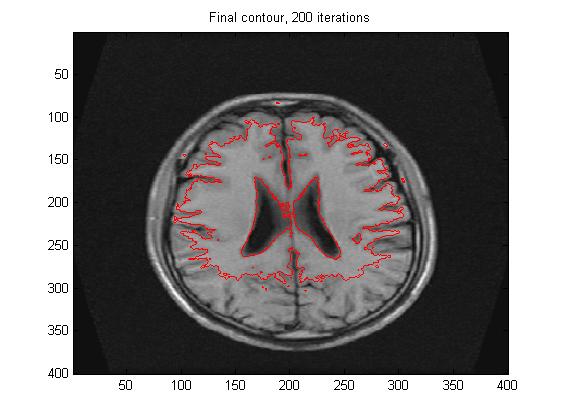

figure;

imagesc(Img, [0, 255]);colormap(gray);hold on;

contour(u,[0 0],'r');

totalIterNum=[num2str(k), ' iterations'];

title(['Final contour, ', totalIterNum]);

四、运行结果